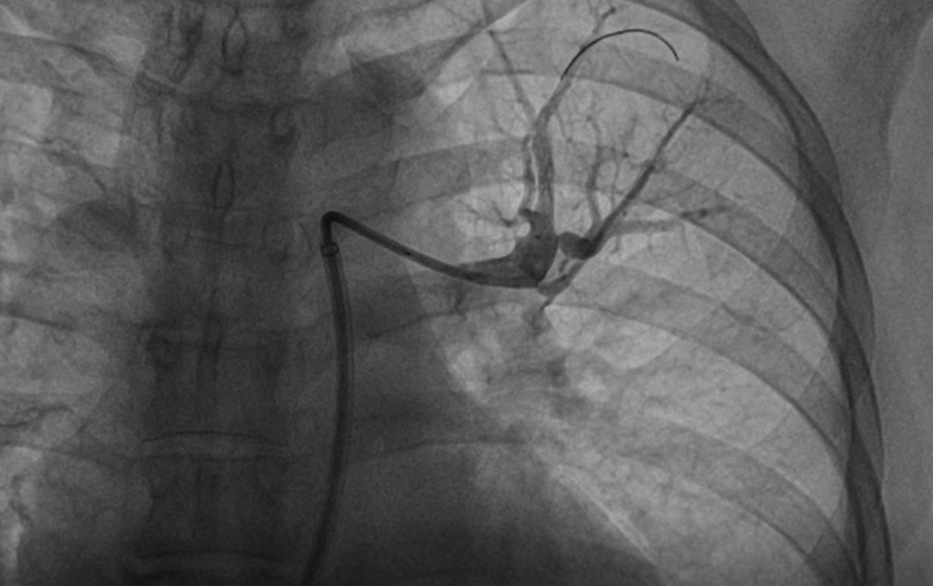

患者慕名至我院后,我科专家进一步对其进行了相关检查,最终诊断为:慢性血栓栓塞性肺动脉高压。心内科周亚峰副院长、陈弹主任、赵良平主任及团队成员进行深入讨论,并邀请呼吸科、血管外科与介入科等进行多学科(MDT)会诊,最终决定对其进行右心导管及肺动脉造影检查,结果提示肺动脉收缩压52mmHg,平均肺动脉压33mmHg,左右各肺动脉及其分支多发栓塞,可见多处血栓影及马赛克征。对右肺动脉A3、左肺动脉A1+2、左肺动脉A9行球囊扩张术,扩张后复查造影远端血流恢复良好。手术后患者的症状得到明显改善,心功能逐渐恢复,住院5天后平稳出院。出院后患者继续进行家庭氧疗、抗凝、利奥西呱降肺动脉压力等治疗,并密切随访中。随访至今,患者情况良好。

右肺动脉A3扩张前